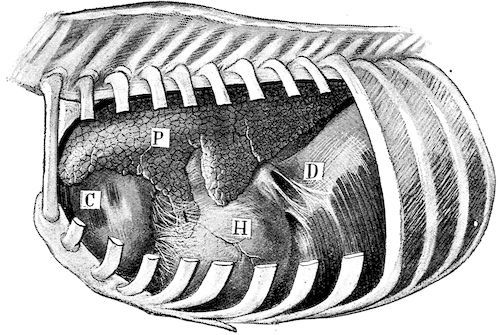

Fig. 9.—C, horn; P, modified skin forming the keratogenous membrane; O, horn core, exhibiting a double sinus.